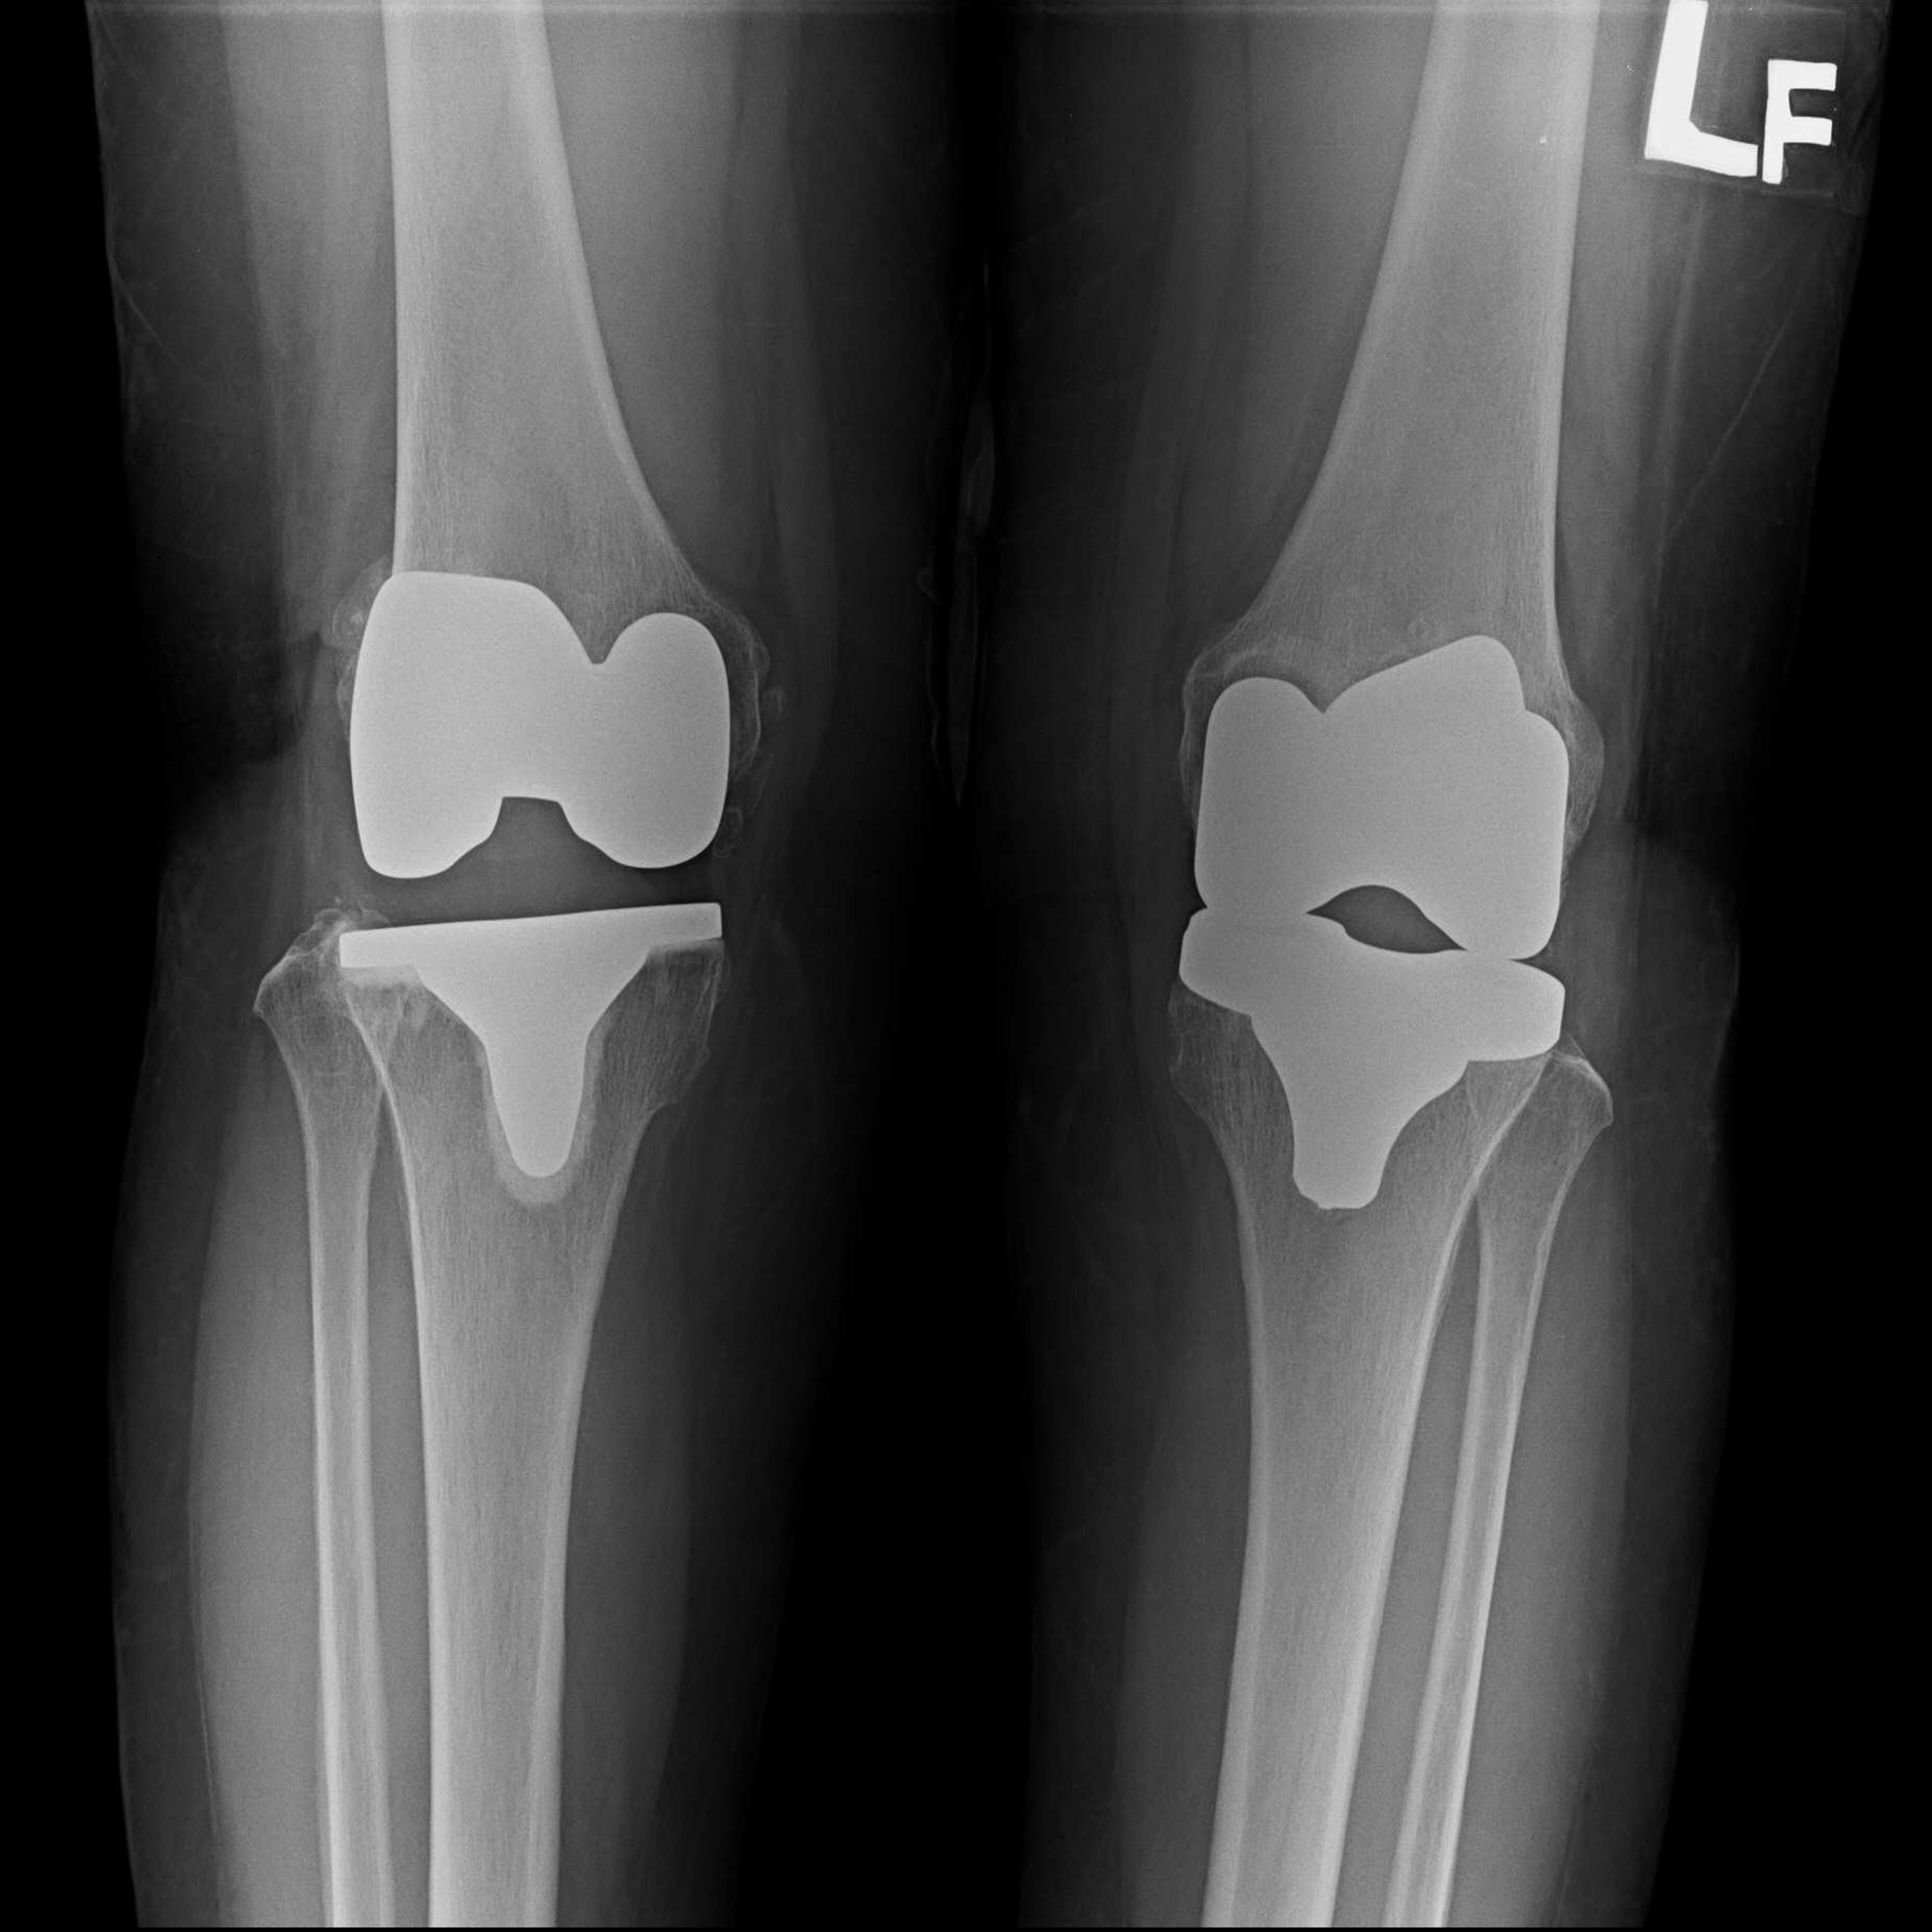

外院失敗本院再置換 首頁 案例分享 膝關節手術 外院失敗本院再置換 蕭女士 69歲 術前 術後 81歲 林女士 術前 術後 蕭女士 69歲 術前 術後 鄒女士 69歲 術前 術後 李女士 74歲 術前 術後 吳女士 71歲 術前 術後 謝女士 65歲 術前 術後